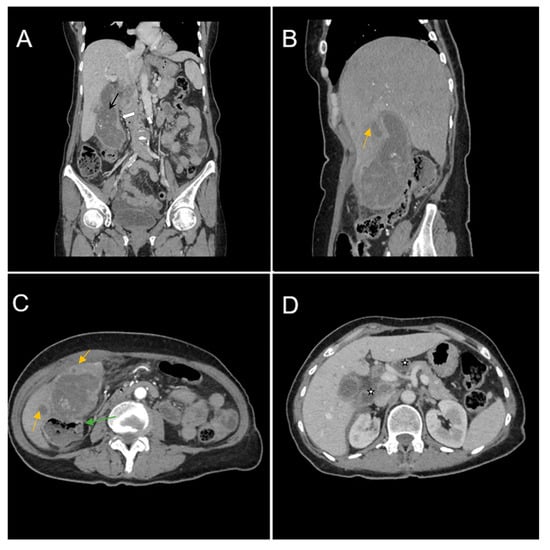

We hereby fully illustrate the case of a 67-year-old female patient, who was admitted to the Emergency Department with intense pain localized in the right renal fossa, radiating to the right abdominal flank, accompanied by nausea with an onset of approximately two weeks. During the physical examination, a reduced abdominal wall mobility with respiratory movements was observed, along with pain in the right hypochondrium and muscular defense. Her medical history included hypertension grade 3 and congestive heart failure. Laboratory tests showed elevated inflammatory markers (leukocytosis, procalcitonin, CRP) and hypochromic microcytic anemia.

Biphasic (arterial phase followed by venous phase) contrast-enhanced emergency CT was performed (Figure 1), which clearly highlighted a gallbladder hydrops, with asymmetric, irregular gallbladder mural thickening, associated with multiple intraluminal mixed stones (Panel A). The tumoral mass extends directly into the adjacent liver parenchyma in segments IV and V and is in contact with the ascending colon (Panel C). Hepatomegaly can be observed (right hepatic lobe measures = 190 mm), with nodular lesions, disseminated in both hepatic lobes, hypodense, with rim peripheral contrast enhancement, more numerous in the right lobe, presenting various sizes (up to 35 mm in segment V) highly suggestive of liver metastases (Panel B and Panel C). Lymphatic metastases are common in gallbladder cancer. In this particular case, CT showed multiple lymph nodes enlargements in the hilar, mesenteric, celiac and precaval regions, up to 26/25 mm (measured in the hepatic hilum), with associated central necrosis (Panel D).

The patient was transferred to the General Surgery Department for specialized treatment (intravenous antibiotics, intravenous hydration and correction of electrolyte abnormalities). After laparoscopy and laparotomy, a subhepatic perforated tumor with duodenum and transvers colon invasion was revealed. A partial cholecystectomy was performed with cholecystostomy and intraperitoneal drain. The postoperative evolution progressed without incident.

Formalin-fixed paraffin-embedded tissue sections from gallbladder and liver were examined histologically. The microscopic description was suggestive of poorly differentiated gallbladder adenocarcinoma (G3); pT3NxMx. The liver metastatic site was pathologically confirmed. TNM according to the AJCC (American Joint Committee on Cancer) 8th edition gallbladder cancer staging system was in this case T3N2M1. Oncology follow-up and adjuvant chemotherapy were recommended.

Figure 1. Multiplanar sections of contrast-enhanced CT acquisitions richly illustrating a low differentiated gallbladder adenocarcinoma. (A) Gallbladder hydrops (>40 mm transverse measurement, 142 mm longitudinal measurement) with asymmetric gallbladder mural thickening, 7 mm (white arrow), and multiple intraluminal mixed stones, 5–8 mm (black arrow). (B,C) Liver metastases—hypodense nodular hepatic lesions with rim contrast enhancement (yellow arrow). (C) Tumoral extension into IV, V segments of the right hepatic lobe and contact with the ascending colon (green arrow). (D) Lymphatic metastases (white stars).